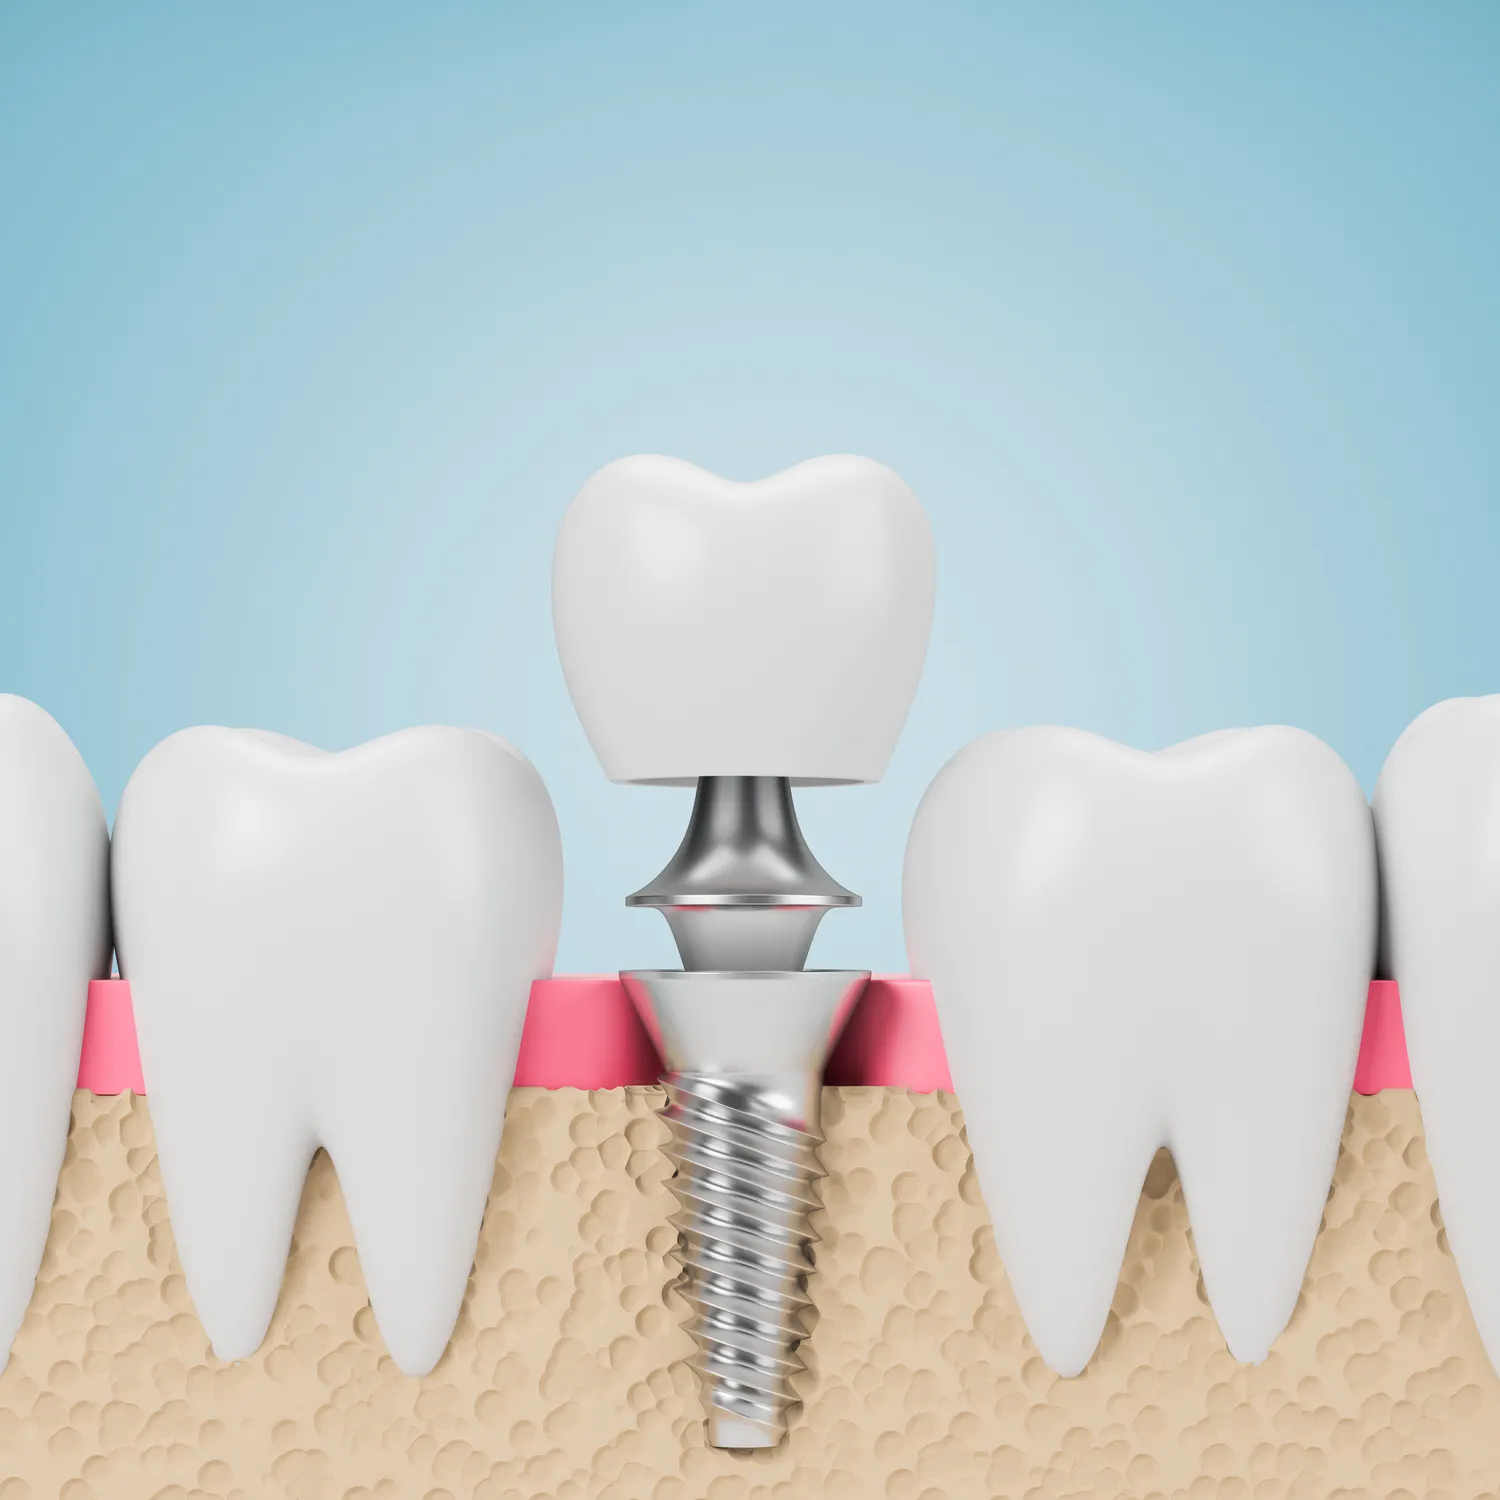

Leczenie zębów w jeden dzień to innowacyjna metoda, która zyskuje na popularności w Koszalinie. Dzięki nowoczesnym technologiom oraz zaawansowanym procedurom dentystycznym pacjenci mogą cieszyć się pięknym uśmiechem już po jednej wizycie. Proces ten zazwyczaj rozpoczyna się od dokładnej diagnostyki, która obejmuje zdjęcia rentgenowskie oraz szczegółowe badania jamy ustnej. Dentysta ocenia stan zębów i dziąseł, a następnie przedstawia pacjentowi plan leczenia. W przypadku konieczności usunięcia zębów lub przeprowadzenia implantacji, wszystkie te zabiegi są wykonywane w tym samym dniu. Dzięki zastosowaniu technologii CAD/CAM możliwe jest szybkie zaprojektowanie i wykonanie koron czy mostów protetycznych, co znacznie przyspiesza cały proces.

Leczenie zębów w jeden dzień w Koszalinie opiera się na zastosowaniu nowoczesnych technologii, które znacznie zwiększają efektywność i komfort zabiegów. Jednym z kluczowych elementów jest technologia CAD/CAM, która umożliwia cyfrowe projektowanie i produkcję uzupełnień protetycznych. Dzięki temu dentysta może szybko stworzyć model zęba, a następnie wykonać koronę czy most w ciągu kilku godzin. To znacząco skraca czas oczekiwania na gotowe uzupełnienie, co jest szczególnie ważne dla pacjentów pragnących uniknąć wielokrotnych wizyt. Kolejnym istotnym narzędziem jest tomografia komputerowa, która pozwala na dokładną ocenę struktury kości oraz lokalizacji nerwów, co jest niezbędne przy planowaniu implantacji. Dzięki temu lekarze mogą precyzyjnie zaplanować zabieg, minimalizując ryzyko powikłań. Warto również wspomnieć o laserach dentystycznych, które są coraz częściej wykorzystywane do leczenia chorób dziąseł oraz przeprowadzania zabiegów chirurgicznych.